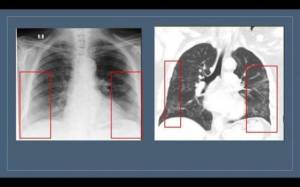

Hətta bəzi hallarda heç bir ciddi narahatçılığı olmayan, amma ya bu infeksiyaya görə PZR testinin nəticəsi pozitiv olduğuna, ya da COVİD-19 olan xəstə ilə təmasda olduğuna görə döş qəfəsi orqanlarının kompyüter tomoqrafiyası olunan şəxslərdə koronavirus pnevmoniyası üçün xarakrterik olan – hər iki ağciyərin aşağı payında, subplevral lokalizasiyalı “buzlu şüşə” görüntüsü müəyyən edilir.

Onu da qeyd edim ki, “buzlu şüşə” görüntüsü yeni deyil və yalnız koronavirus zamanı yox, ağciyərlərin müxtəlif mənşəli iltihabi proseslərində də aşkar edilir.